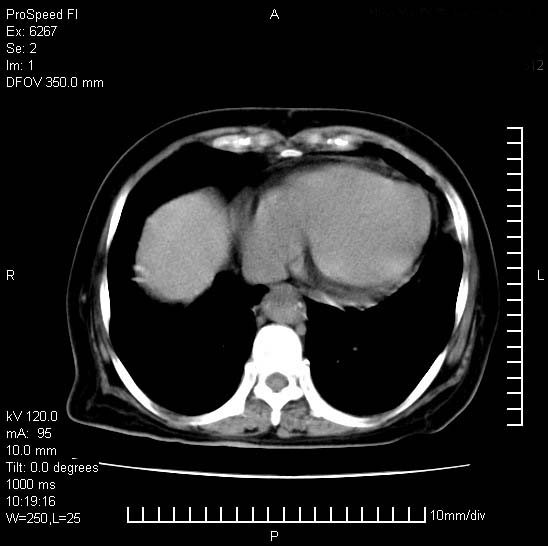

患者糖尿病,腹痛,恶心,呕吐。黄疸,意识较差,血糖很低(数值不详),临床以胆囊,胆管炎,低血糖反应收治。看的腹片少,各位帮忙看看,胰腺有问题吗??

胆囊炎,胆石症;胰腺炎可以确定,但需要增强,除外肿瘤

1.胰腺体积增大,胰周脂肪间隙消失,胰腺炎可以确定。必要时实验室进一步检查。

考虑胰腺炎。胆囊炎,胆石症。脾大。

1)考虑胰腺炎;建议查血尿淀粉酶。2)胆囊炎,胆囊结石。3)脾大。